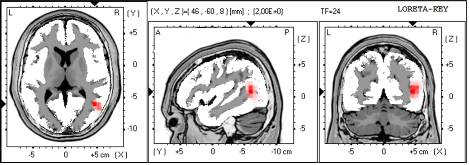

Medición previa (q-EEG)

El EEG cuantitativo (q-EEG) es un conjunto de métodos estadísticos utilizados para analizar y evaluar el EEG (ondas cerebrales). Produce medidas de cada una de las ubicaciones del cuero cabelludo, describiendo la cantidad o potencia para cada frecuencia de onda cerebral o grupos de frecuencias llamadas bandas. El método consiste en realizar inicialmente una medición, con un electroencefalograma que será procesado y cuantificado (q-EEG), lo que permite determinar las áreas cerebrales en las que se realizará el tratamiento. Con esta medición, obtenemos las regiones cerebrales que están funcionando de un modo alterado, causando síntomas y dificultades. A partir de esta información, se elabora un protocolo de entrenamiento específico para cada persona. El q-EEG nos servirá además, para la comparación de la evolución obtenida pre y post tratamiento.